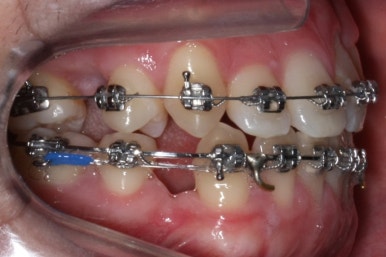

악궁확장과 동반하여 부산구순구개열 키다리아저씨치과에서는 브라켓을 부착하여 가지런하게 하는 작업을 시작하였습니다.

위아랫니가 각각 가지런해지고 있는 것을 볼 수 있습니다.

윗니는 아직 가지런하게 하는 작업 중이며, 아랫니는 가지런하게 하는 작업은 거의 다 되었습니다.

계속 윗니는 가지런히 해주고 있으며 아랫니는 앞뒤를 뒤로 당기고 있습니다.

거꾸로 물리던 앞니가 서서히 개선되어 가는 것을 볼 수 있습니다.

부산구순구개열 키다리아저씨치과에서 교정치료 하신지 1년여만에 드디어 앞니는 거꾸로 넘어왔고, 윗니들도 상당히 많이 가지런해졌습니다.

이 뽑은 자리도 상당히 많이 줄어든 것을 볼 수 있고, 이제는 정상적인 포개짐이 만들어졌습니다.